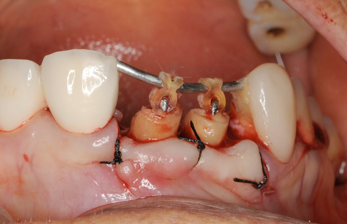

歯が折れて根っ子が少しだけ歯茎からでている状態。

虫歯でもそうですが、こうなるとこのまま差し歯をいれてもすぐ外れるといったトラブルが起こります

歯が1ヶ月くらいで出てきますが、歯茎もいっしょに出てくるので、余分な歯茎を取り除きます